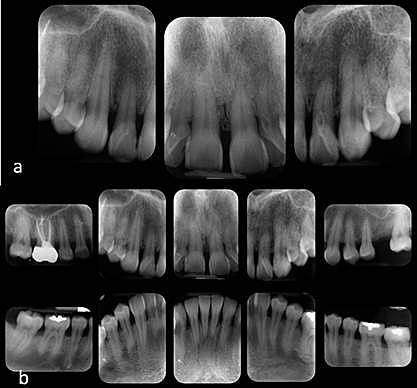

• Análisis radiográfico por serie periapical.

Análisis radiográfico por serie periapical.

Px acude para la toma de serie radiográfica.